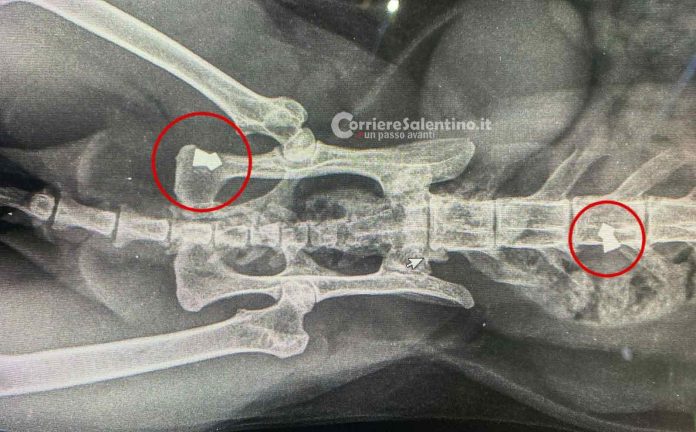

Salento, gatti colpiti da piombini esplosi con una carabina: “La cattiveria umana non ha limiti”